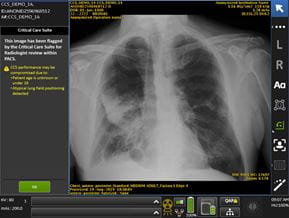

Chest scanUH Department of Radiology implemented two AI tools for automated endotracheal tube detection and the Critical Care Suite with pneumothorax on the clinical PACS system. In collaboration with GE Healthcare, UH was the first site in the US to implement these improvements in the healthcare system. We continue to work in partnership with GE on multiple AI projects expanding overall patient populations.